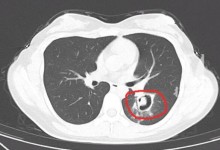

杭州姑娘清理发霉衣柜肺部长霉菌 清理时没做好防护-融党建互动平台

杭州姑娘清理发霉衣柜肺部长霉菌 清理时没做好防护

admin阅读(131)赞(0)

一周前,家住杭州的“00后”王小姐(化名)出现咳嗽、乏力,还发热,最高到了40度。情况不妙,王小姐被朋友送去了附近的杭州师范大学附属医院。经过一系列检查,医生从肺部CT上发现,王小姐的肺部长出了一个个&ldquo...